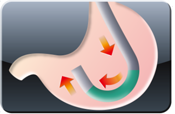

Curvatura Adaptável – Gastro Capacidade de Curvatura Inferior de 160°

Tecnologia 4K O gastroscópio terapêutico slim EG-840TP é equipado com o sensor CMOS e oferece angulação de 160° para baixo, permitindo o acesso a áreas de difícil alcance. Seu canal de trabalho de 3,2 mm proporciona um bom equilíbrio entre desempenho de sucção e controle dos instrumentos inseridos, tornando-o altamente indicado para intervenções terapêuticas avançadas, como a ESD.